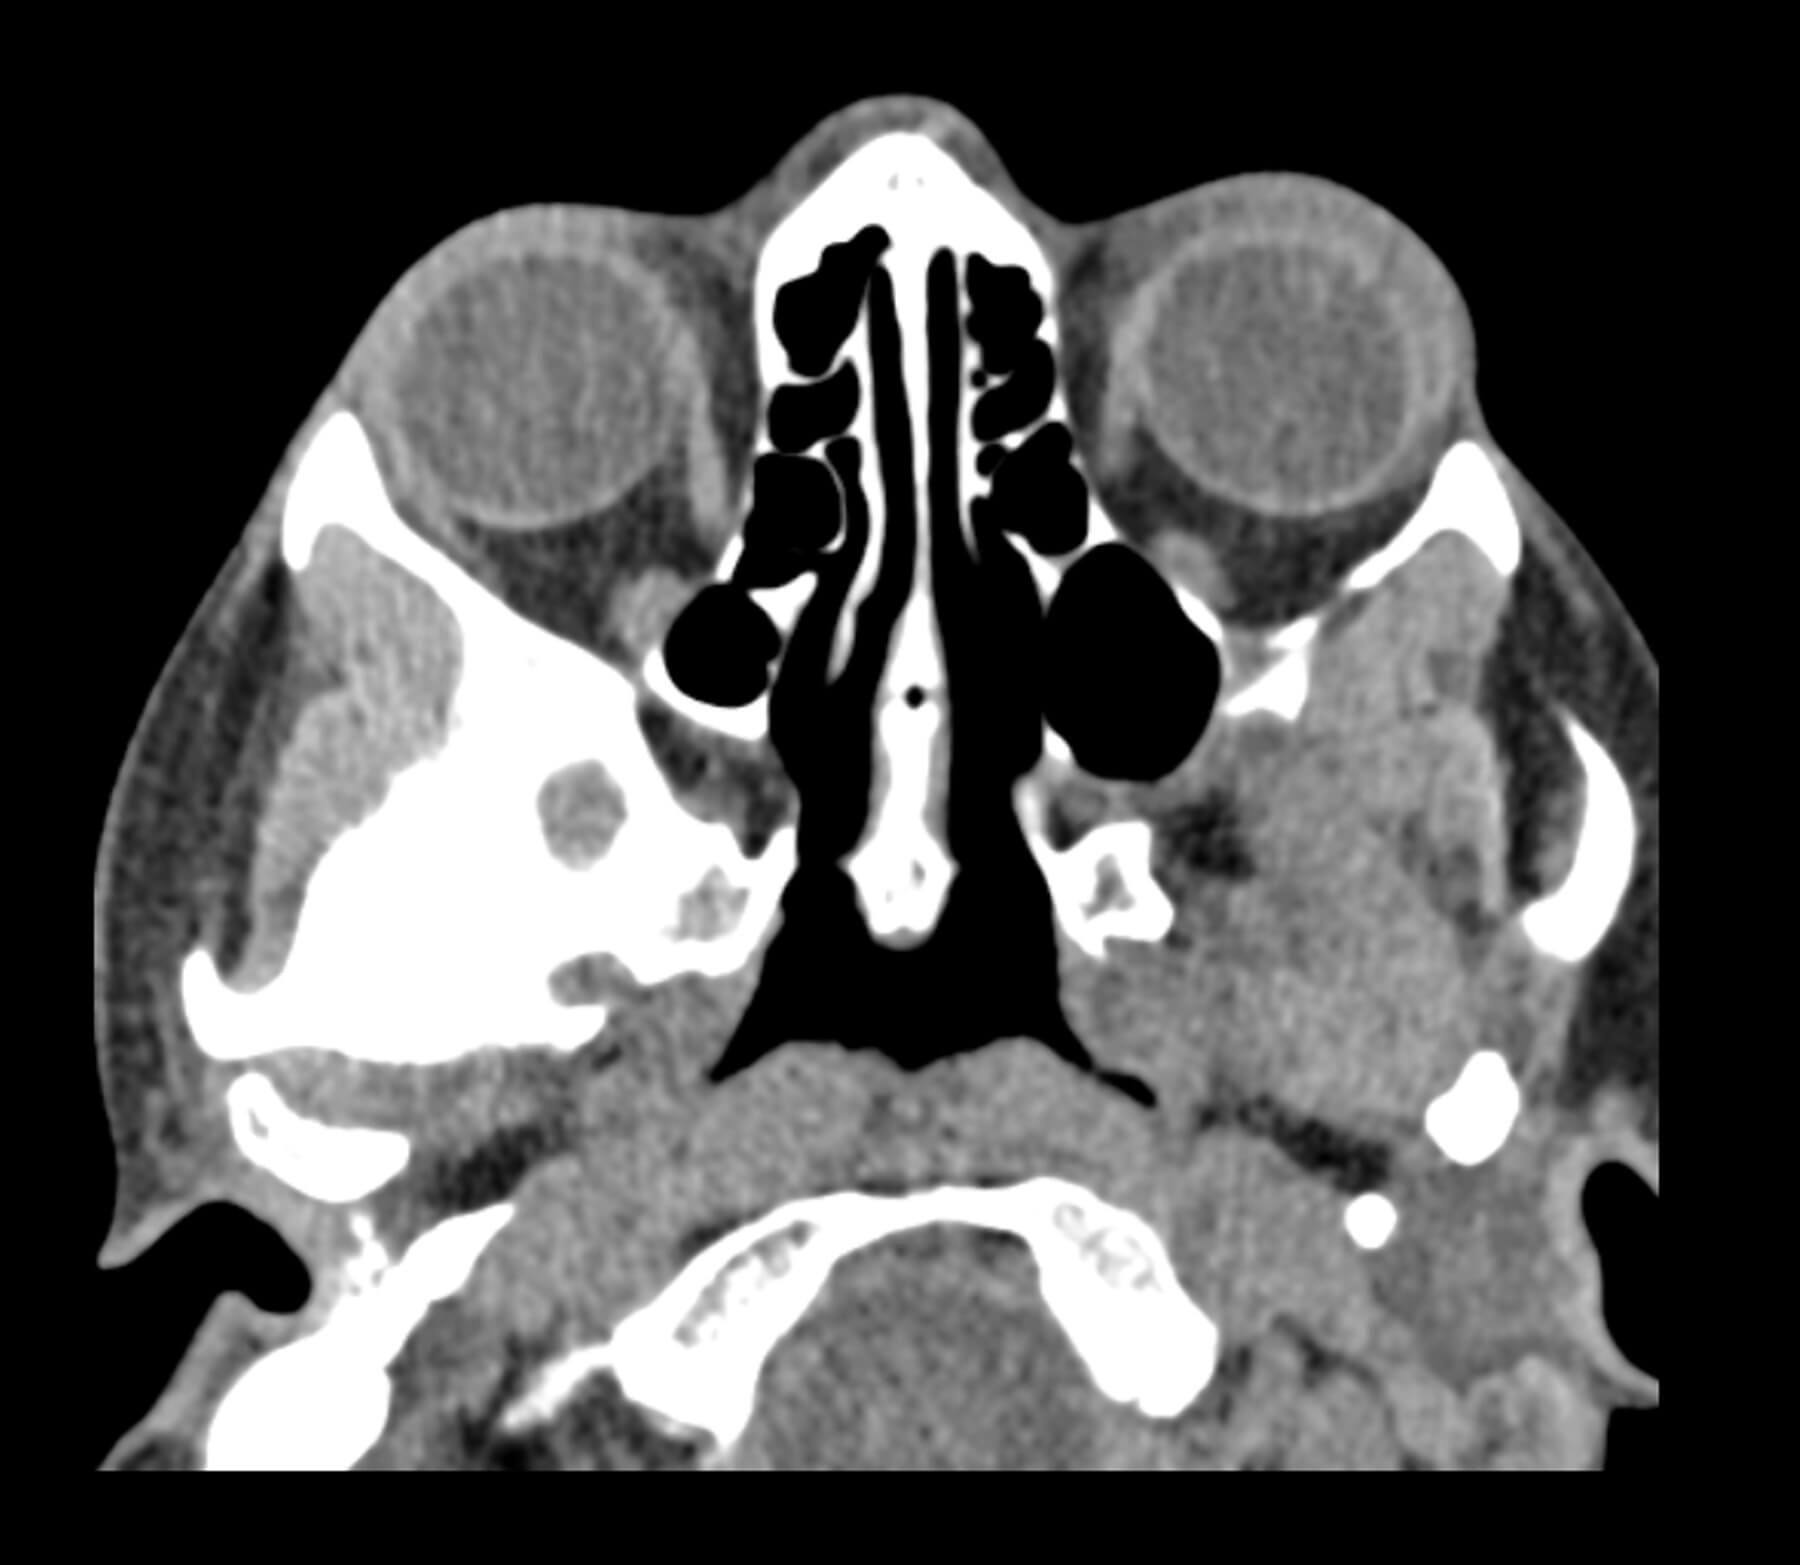

Figure 2a: CT facial bones, brain, sinuses without contrast - thin, soft.

Computed tomography (CT) imaging showed no acute intracranial abnormality with minimal periorbital haemorrhage without evidence of significant optic nerve compression. Despite this, clinical findings strongly indicated OCS, prompting the decision to proceed with an emergency LCC.